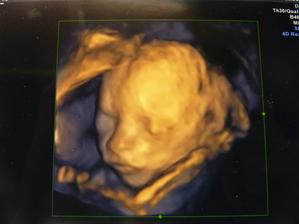

Jmenuju se Michal a narodil jsem se v pátek 13. února 2009 ve 13:54 hodin v porodnici ve Vsetíně s mírami 3750 gramů a 53 centimetrů * ve čtvrtek 19. února nás konečně pustili domů * 26. února jsem byl poprvé v poradně a protože jsem velký gurmán, vážím už 4170 gramů a měřím 54 centimetry * 19. března váha ukázala 5130 gramů a povyrostl jsem se na 58 centimetrů * jsou mi dva měsíce a moje míry jsou 5850 gramů a 61 centimetr, přestaly mně trápit prdíky, už bylo na čase 🙂) * 19. května - 6740 gramů a 64 centimetry, kdyby měl zhojené očkování po TBC, mohl jsem dnes dostat první Hexu, takhle ale musíme počkat * 16. června už vážím úctyhodných 7490 gramů a měřím 66 centimetrů * poradna 14. července - 8550 gramů a 70 centimetrů; začal jsem večer dostávat k mlíčku taky trochu kašičky a mooooc mi chutná * 11. srpna jsem byl na půlroční prohlídce, jsem velký šikula a to velký je fakt na místě - 9220 gramů a 70 centimetrů 🙂) začal jsem papat zeleninku a taky masíčko a všechno mi to mooooc chutná, jenom ovoce fakt nemusím 🙂 * 8. září a 9690 gramů * 25. září jsem vycestoval za hranice do sousedního Slovenska a pár dnů jsem si užíval v Tatrách, bylo to žůžo * 13. října jsem překonal deset kilo - 10170 gramů a 74 centimetry * je mi rok, vážím 11250 gramů a měřím 82 centimetry 🙂 * 25. března jsem začal sám chodit *